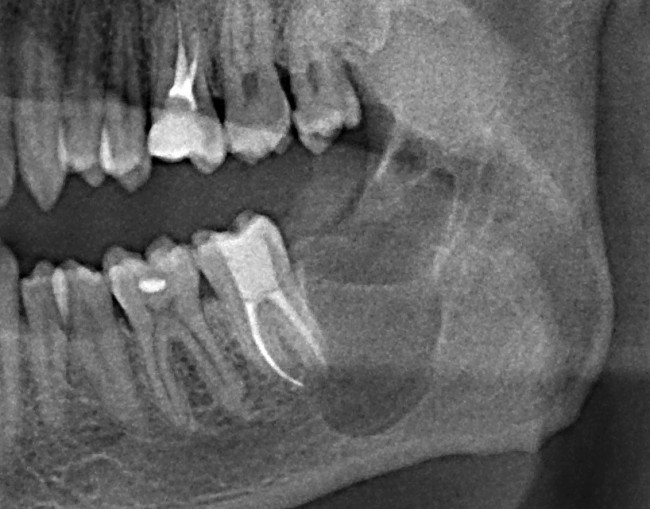

Проблема решена. Пациент счастлив. А ведь всего этого можно было избежать, сходив планово на осмотр к стоматологу.

Вот такая картина нас ждала спустя год после удаления. Все затянулось. Все прекрасно!

А грозить это могло как переломом челюсти, так и поражением нижнечелюстного нерва, которое сопровождается онемением губы и подбородка со стороны причинного зуба, а онемение это может остаться на всю жизнь.